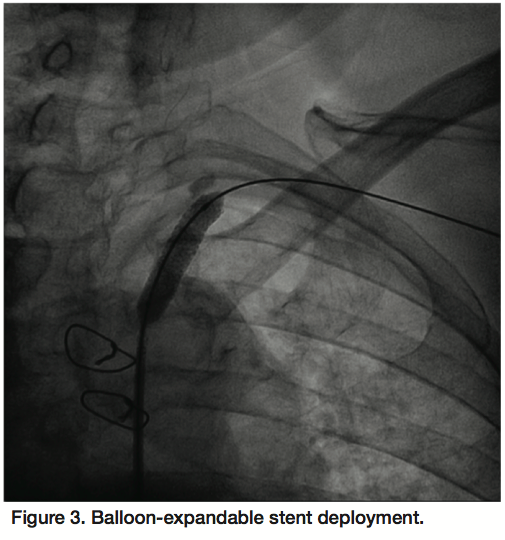

A 6 Fr, 65 cm sheath (Terumo Corporation, Tokyo, Japan) was used to engage the origin of the left subclavian artery via the right femoral artery. Unfractionated heparin anticoagulation was used during the procedure. A V18 Control Wire guidewire (Boston Scientific) crossed the severely calcified, eccentric lesion in the subclavian artery. An AngioSculpt 4 x 40 mm scoring balloon catheter (AngioScore) was used for predilatation given the calcific burden of the lesion (12 atm, 40 seconds) (Figure 2). The V18 guidewire was then exchanged for a Supra Core 0.035 guidewire (Abbott Vascular) over which a subsequent predilatation was performed with a 5 x 40 mm FoxCross balloon (Abbott) (9 atm, 30 seconds). An Express LD 8 x 27 mm balloon-expandable stent (Boston Scientific) was deployed (10 atm, 20 seconds) (Figure 3) and postdilatation was performed with a 9 x 20 mm Admiral Xtreme balloon (Invatec, Medtronic, 9 atm, 20 seconds). An excellent angiographic result was achieved (Figure 4) with minimal residual left subclavian stenosis and no gradient across the lesion. In addition, at the end of the procedure there was angiographic evidence of antegrade left vertebral artery flow and more brisk filling of the LIMA. The patient’s symptoms of angina and left upper extremity claudication resolved and he remained symptom-free at his 6-month follow-up interview.